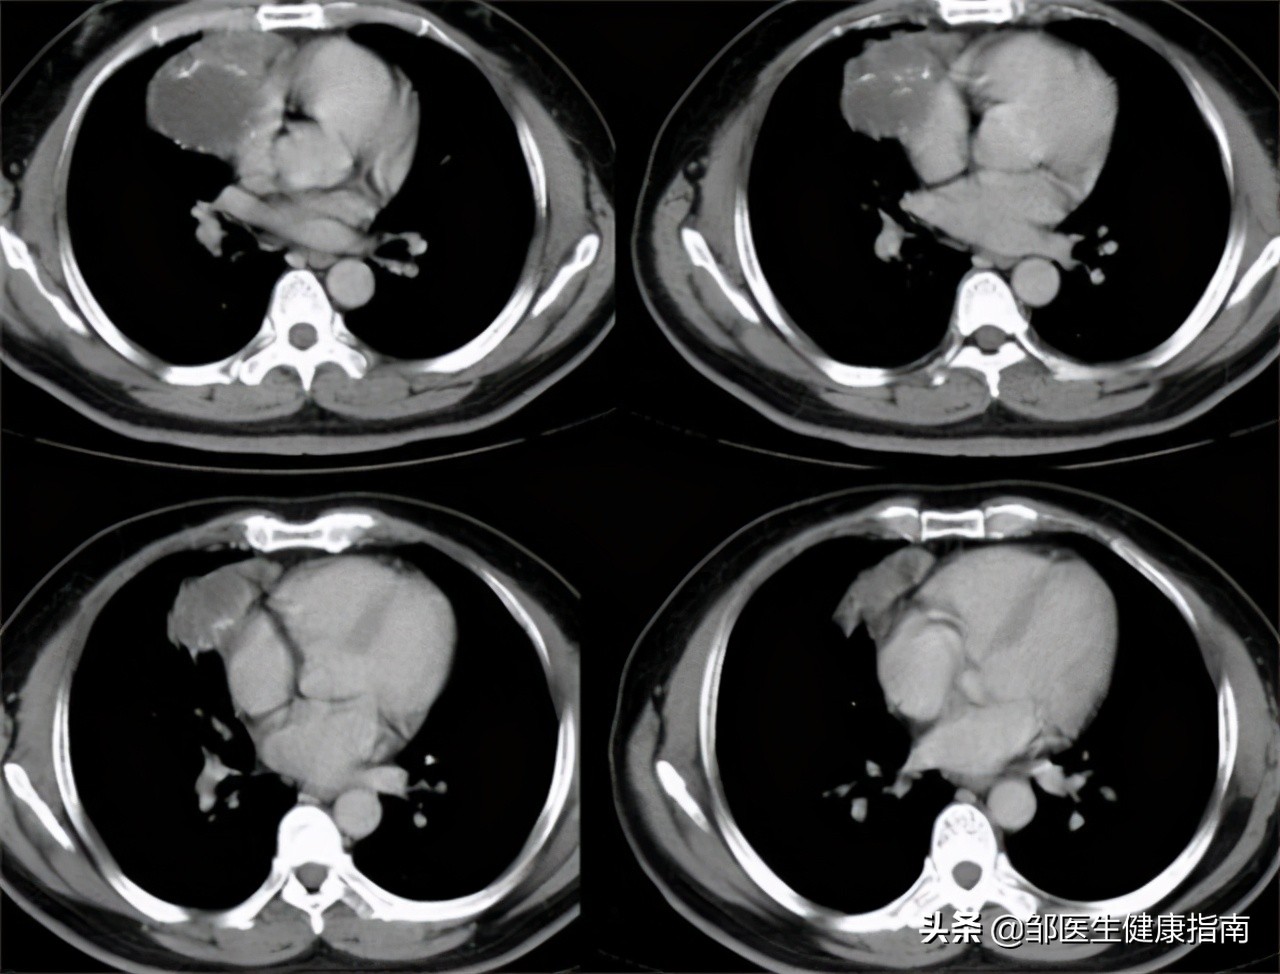

患者体温36.4℃、血压114/80、身高162cm、体重70kg。患者下腹部可触碰到坚硬包块,腹部存在少量腹水。B超提示右下腹囊实性回声包块,大小约85mm*52mm*68mm,伴其旁混合偏低回声,考虑为卵巢畸胎瘤伴蒂扭转可能。肿瘤标志物检查49%甲胎蛋白阳性,可确诊为良性畸胎瘤。